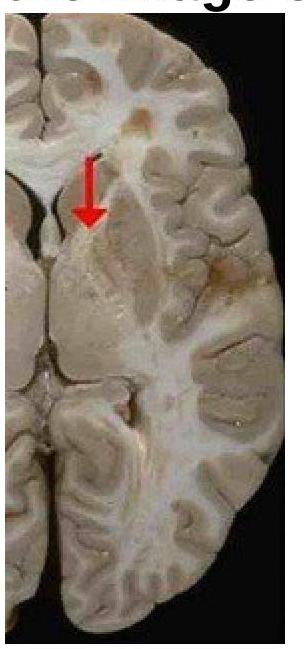

Explanation: ***Projection fibers*** - The image shows the **internal capsule**, which is a white matter structure composed of **projection fibers** that connect the cerebral cortex to subcortical structures, brainstem, and spinal cord. - These fibers facilitate communication between different levels of the central nervous system, including motor and sensory pathways. *Short association fibers* - These fibers, also known as **U-fibers**, connect adjacent gyri within the **same cerebral hemisphere**. - They are typically located superficially in the cerebral cortex, not deep within the brain as shown in the internal capsule. *Long association fibers* - These fibers connect **different lobes** within the **same cerebral hemisphere**, such as the arcuate fasciculus connecting temporal and frontal lobes. - While they are white matter tracts, they do not constitute the internal capsule, which is specifically known for its extensive projection pathways. *Commissural fibers* - **Commissural fibers** connect corresponding areas in the **two cerebral hemispheres**, with the most prominent example being the **corpus callosum**. - The internal capsule, shown in the image, primarily consists of fibers projecting superiorly and inferiorly, rather than horizontally across hemispheres.